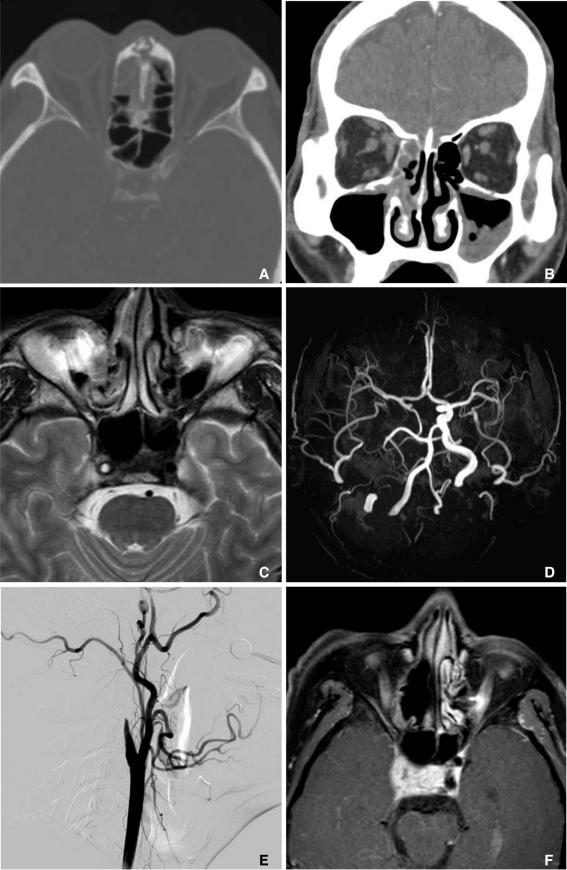

Rhinocerebral mucormycosis is an acute fulminant opportunistic fungal infection usually seen in diabetic or immunocompromised patients. The fungi that cause mucormycosis inoculate the nasal mucosa and may spread to the paranasal sinuses, orbit, and brain. Our patient initially presented with mild ethmoid sinusitis. At that time, brain MRI and contrast-enhanced MR angiography were grossly normal. However, aggravation of sinusitis with extension to the right orbit and anterior cranial fossa rapidly developed within two months. Moreover, an occlusion of the right internal carotid artery was combined. We report a case of a pathologically-proven rhino-orbital-cerebral mucormycosis with serial follow-up imaging for over one year.

鼻脑型毛霉菌病是一种急性暴发性机会性真菌感染,通常见于糖尿病患者或免疫功能低下者。引起毛霉菌病的真菌侵入鼻粘膜,并可能扩散至鼻窦、眼眶和脑部。我们的患者最初表现为轻度筛窦炎。当时,脑部MRI和对比增强磁共振血管造影大致正常。然而,鼻窦炎在两个月内迅速加重并蔓延至右侧眼眶和前颅窝。此外,还合并了右侧颈内动脉闭塞。我们报告一例经病理证实的鼻眶脑型毛霉菌病病例,并进行了一年多的系列随访影像学检查。